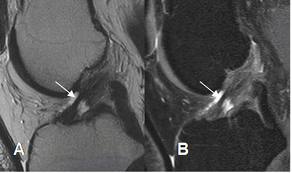

¿Debo operar mi ligamento cruzado anterior parcialmente roto? 06 jueves Dic 2012 Tamaño original 292 × 173 ≈ Deja un comentario RNM rotura parcial